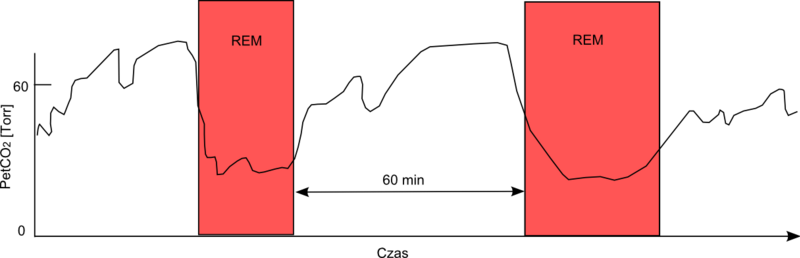

Hypercapnea – is also known as hypercarbia. It is a condition related to high carbon dioxide levels in the body. Carbon-dioxide can get built up in the blood if the body doesn’t successfully get rid of it within time. Conditions that either increase the levels of carbon-dioxide in the body or prevent the waste carbon-dioxide from getting to the lungs and discarded are usually the main causes of hypercapnea. Illnesses related to lung, brain, muscles and nerves are usually the most common causes. Hypercapnia is different to hypoxemia as hypercapnia is the condition with high carbon-dioxide levels in blood whereas hypoxemia is low oxygen levels in blood.

Type II: – involves alveolar hypoventilation resulting in hypercapnia (PaCO2). There is a significant reduction in the alveolar minute ventilation that entails inadequate removal of carbon dioxide.

Acute respiratory failure vs chronic respiratory failure: In type II respiratory failures, there is active vs chronic respiratory failure, active failure matures and progress over minutes to a couple days and involves respiratory acidosis (a condition where lungs are not able to get rid of all the carbon dioxide in the body). On the contrary, chronic failure takes anywhere from days to months to develop and involves a higher PaCO2 including increased levels of serum bicarbonate due to renal compensation.